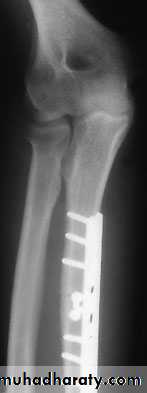

X-ray

A transverse or short oblique fracture is seen in the lower third of the radius, with angulation or overlap. The distal radio-ulnar joint is subluxated or dislocated.

Treatment

As with the Monteggia fracture, the important step is to restore the length of the fractured bone. In children, closed reduction is often successful; in adults, reduction is best achieved by open operation and compression plating of the radius.

Fixation of #